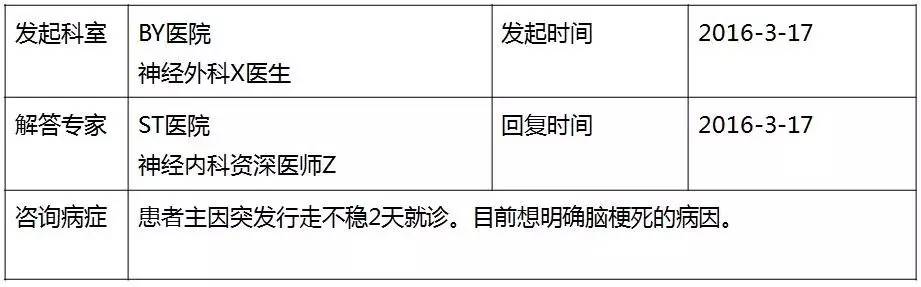

基础信息

▼患者病情描述

▼头MRI(2016-3-6)

▼头DWI(2016-3-6)